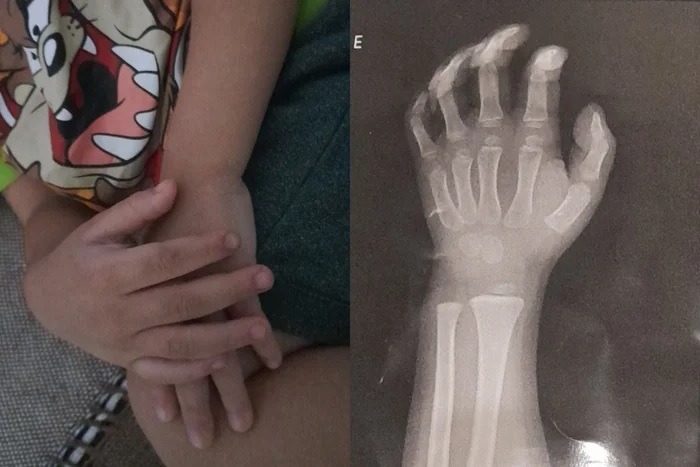

Segundo a Polícia Civil, a agressão aconteceu no dia 28 de maio. A criança chegou em casa com o braço machucado e, após ser levada a uma Unidade de Pronto Atendimento (UPA), foi diagnosticada com luxação.

A Secretaria da Segurança Pública (SSP) informou que exames de corpo de delito foram solicitados para a vítima.